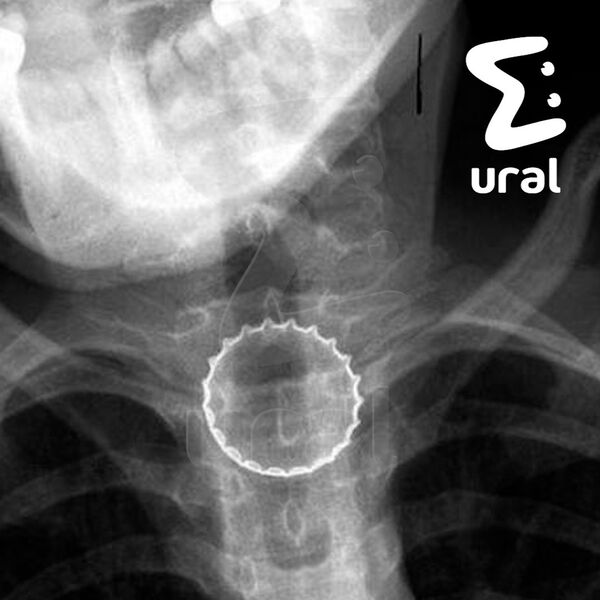

В Челябинске 16-летний подросток случайно проглотил железную крышку от бутылки, ему потребовалась срочная операция. Об этом сообщает Telegram-канал Ural Mash.

По информации Telegram-канала, инцидент произошел, когда несовершеннолетний ловил металлическую крышку губами. Предмет попал ему в горло и застрял в пищеводе.

Медики заключили, что подростку требуется срочная операция в связи с тем, что крышка имела острые края, которые могли порезать внутренние органы несовершеннолетнего.